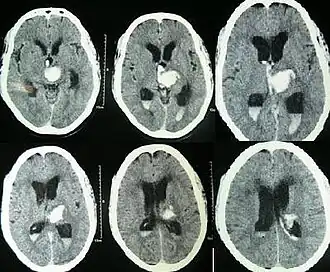

![]() | |

| Hydrocephalus as seen on a CT scan of the brain. The black areas in the middle of the brain (the lateral ventricles) are abnormally large and filled with fluid. | |